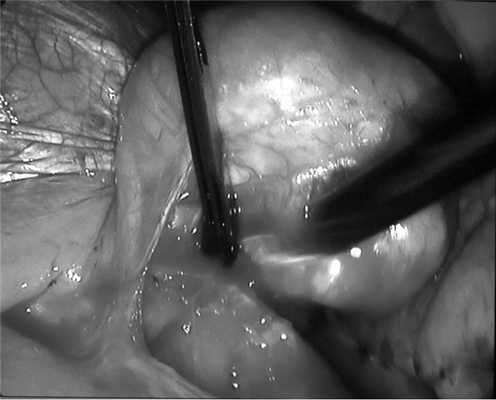

29.09.11 выполнено оперативное вмешательство под эндотрахеальным наркозом с раздельной вентиляцией легких. В положении больной на правом боку установлено 4 торакопорта: в пятом, седьмом и восьмом межреберьях слева. При торакоскопии выявлено опухолевидное образование в проекции нижней легочной связки, оттесняющее нижнюю долю легкого кверху и диафрагму книзу. Образование округлой формы, диаметром до 13 см. С помощью гармонического скальпеля рассечены нижняя легочная связка и медиастинальная плевра над образованием, которое представляло собой опухоль в капсуле и имело плотную дольчатую структуру (рис. 2). С использованием прецизионной техники выполнена энуклеация новообразования с отделением его от слизистой пищевода без вскрытия просвета органа. После удаления опухоли образовался дефект мышечной оболочки пищевода ромбовидной формы длиной 2 см с выбухающей слизистой. На мышечную стенку пищевода в области дефекта наложены узловые швы рассасывающимися нитями. Линия швов дополнительно укреплена лоскутом медиастинальной плевры. С целью контроля качества швов и состояния слизистой пищевода выполнена интраоперационная фиброэзофагоскопия, повреждений не выявлено. Опухоль удалена из плевральной полости через расширенный до 6 см разрез в восьмом межреберье (рис. 3).

Рис. 2. Интраоперационная фотография. Этап мобилизации лейомиомы пищевода.

Рис. 3. Вид операционного поля после завершения торакоскопической операции.

Макроскопически лейомиома представляла собой дольчатую опухоль с перетяжкой посередине, размером 12×7 см, плотной хрящевой консистенции, с включениями кальцинатов в глубине тканей (рис. 4).